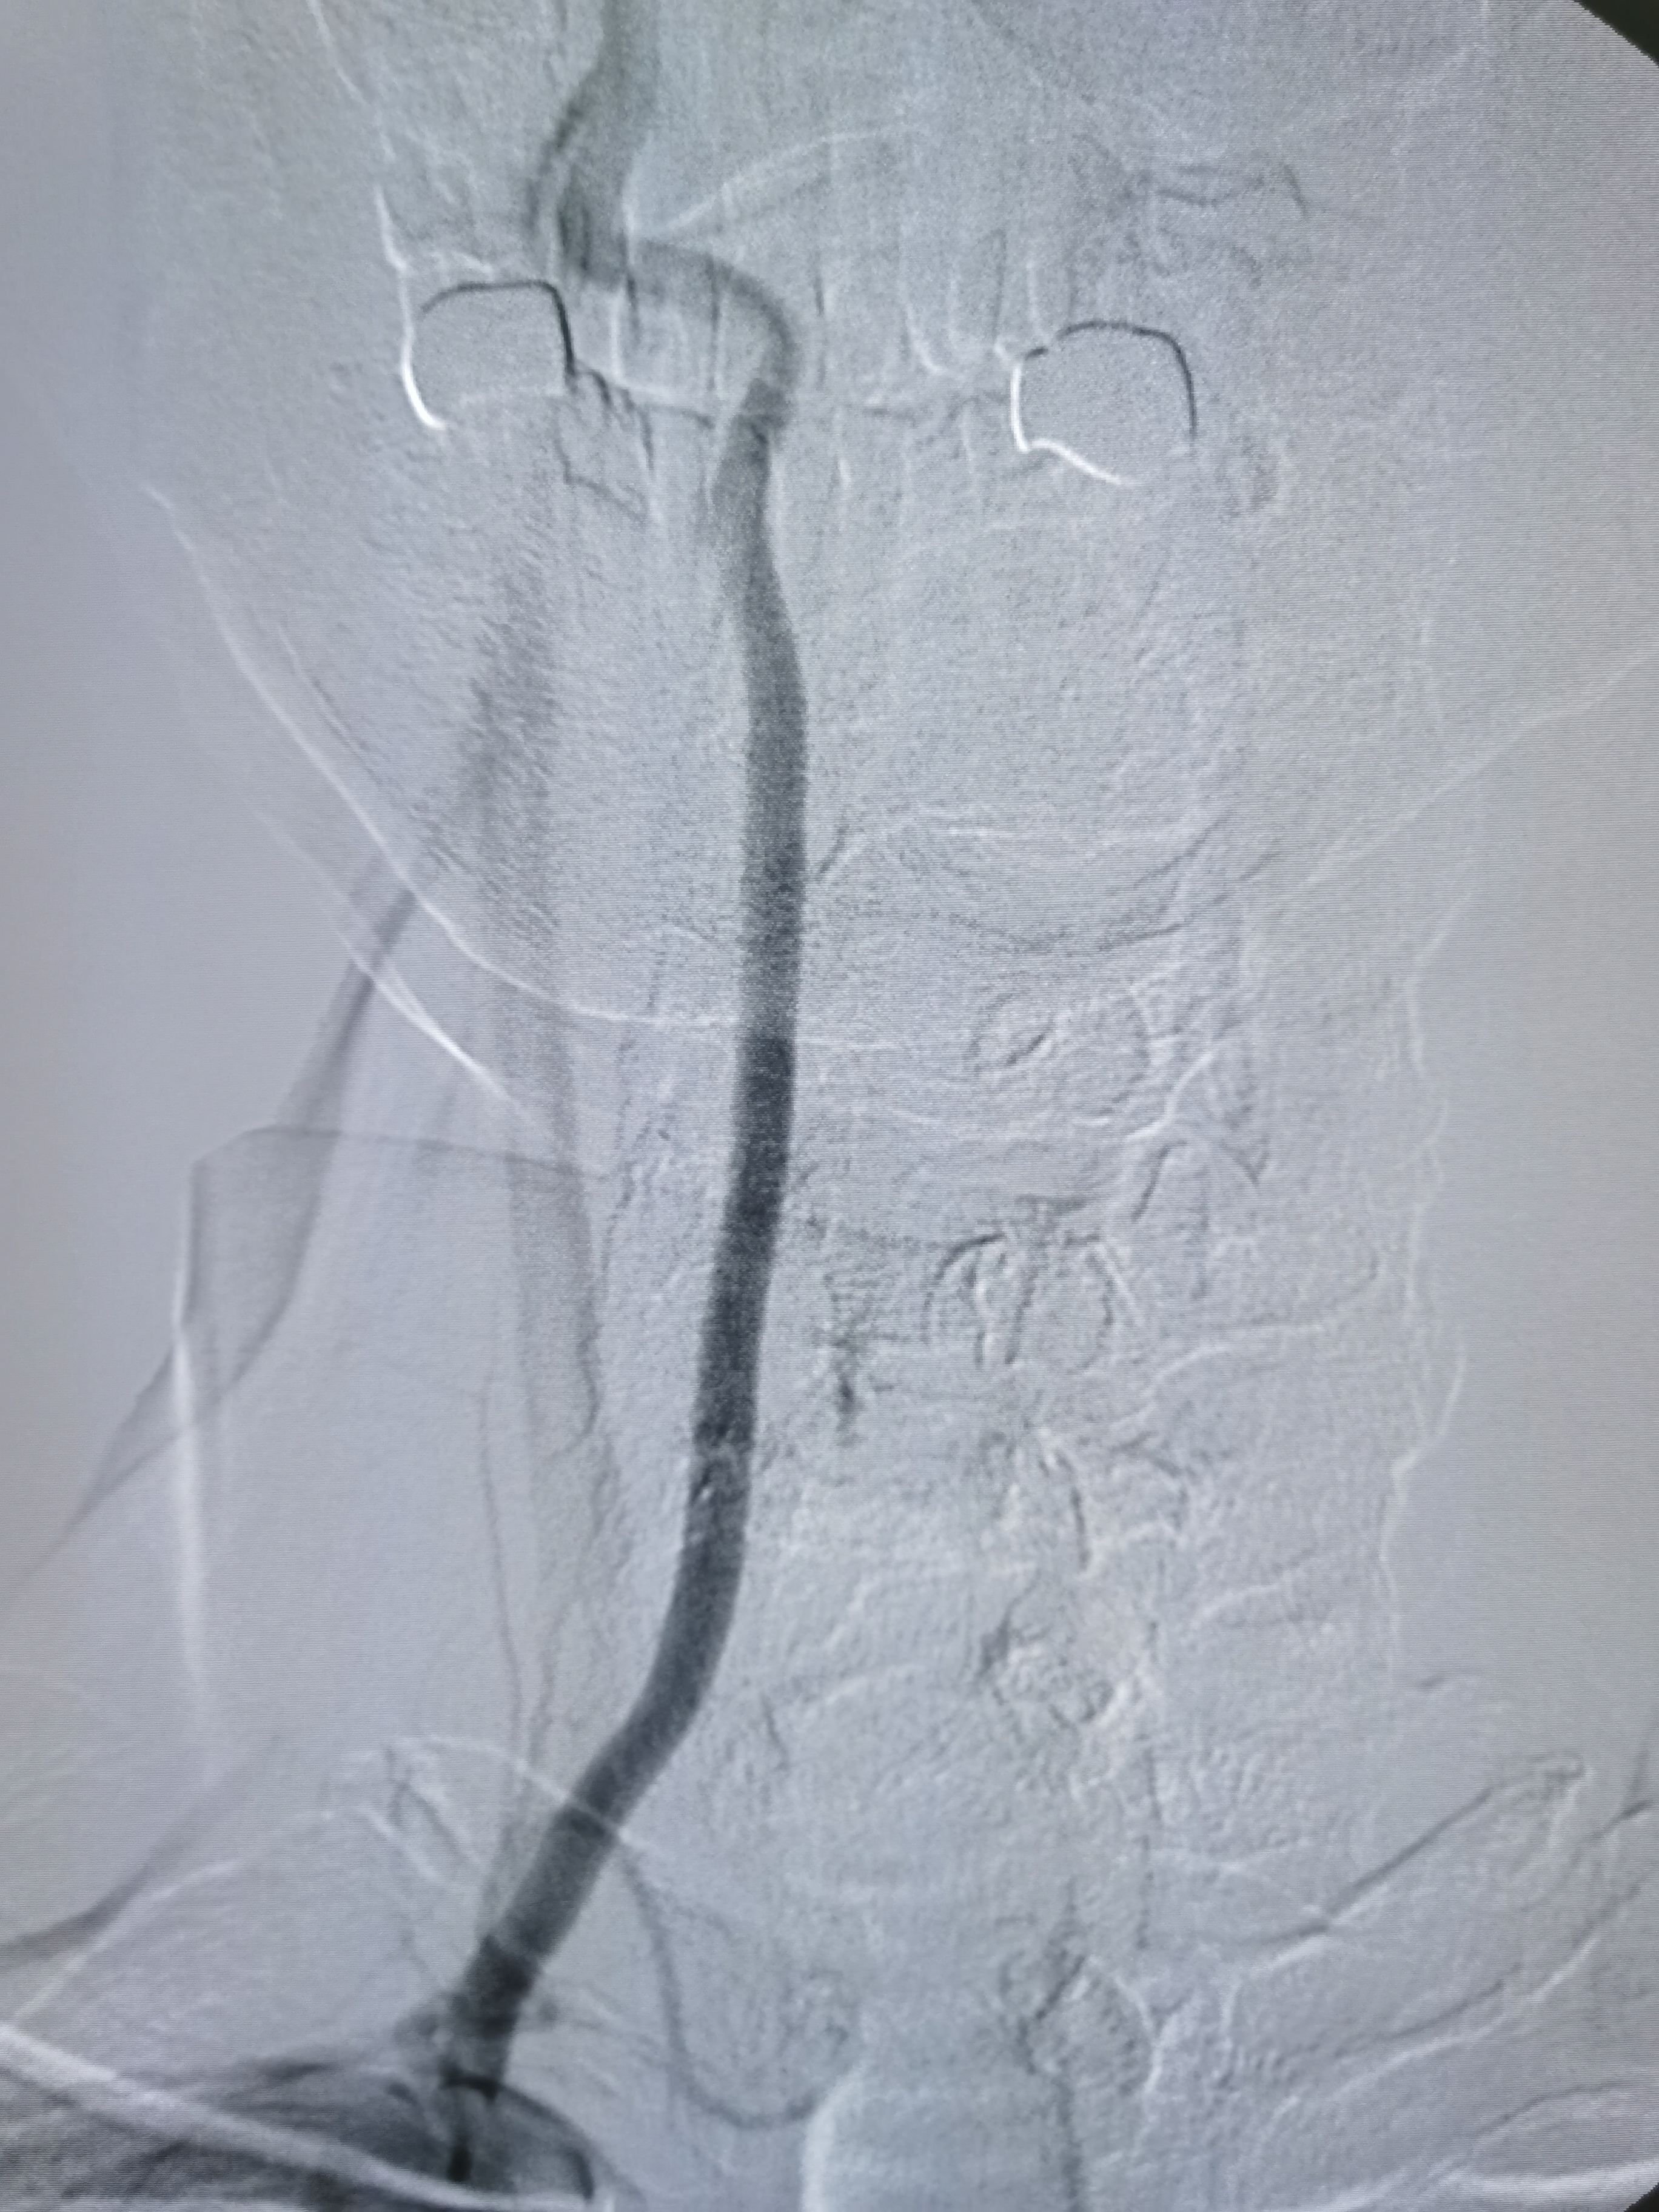

全麻后,将8F导引导管及中间导管顺利到位,建立路径,在路径图下微导丝携微导管顺利通过病变。

微导管确认位于真腔,交换入Transend300导丝。